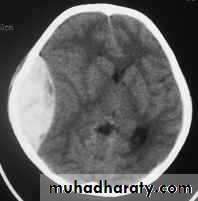

3. Brainstem and hemispheric (Cerebral) Contusion

These are areas of bruising and swellings with intact pia arachnoid, localized or generalized oedema and haemorrhage due to tearing of blood vessels.

3. Cerebral Contusion

Clinical presentations:

1. Prolonged periods of unconsciousness.

2. Focal neurological deficits that persist for longer than 24 hours.

CT scans demonstrates contusions as small areas of haemorrhage in the cerebral parenchyma.

Contusions may resolve with the accompanying deficits or they may persist.